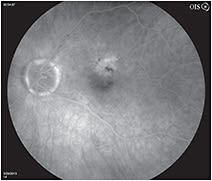

A 79-year old woman complained of decreased visual acuity – from 20/25 to 20/50 – of 5 weeks’ duration. A color fundus photograph of the left eye (Figure 1) showed macular edema and scattered intraretinal hemorrhages. Significant intraretinal dye leakage due to retinal angiomatous proliferation (RAP) was seen on the fluorescein angiogram (Figure 2). The OCT image (Figure 3) demonstrated intraretinal edema with insignificant vitreomacular adhesion. At follow-up, the patient received aflibercept 2 mg intravitreally and returned in 4 weeks for re-evaluation. Her visual acuity had improved to 20/30 and the repeat OCT image (Figure 4) showed complete resolution of the intraretinal edema.

Figure 1